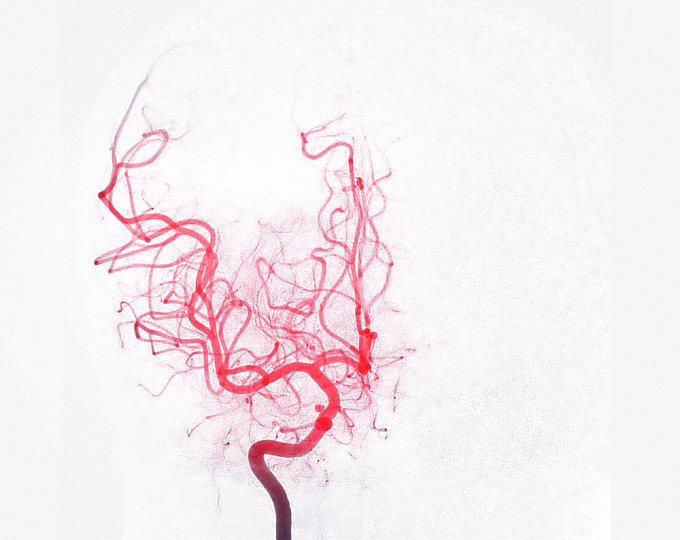

Целью исследования было оценить влияние тревожных и депрессивных расстройств, диагностированных после выявления неразорвавшейся интракраниальной аневризмы, на риск ее разрыва и общую смертность.

В анализ были включены 127 361 взрослый пациент с неразорвавшейся интракраниальной аневризмой.

Сравнивались исходы у пациентов, у которых тревожное расстройство или депрессия были диагностированы в течение 127 дней после выявления аневризмы, с пациентами без этих состояний.